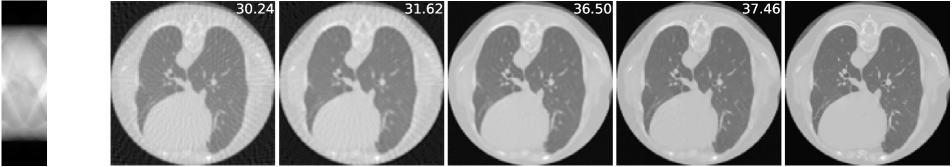

4.2 Sparse-view CT

The imaging physics model of X-ray computed tomography (CT) is the discrete radon transform. The physics model is the radon transformation where 50 views (angles) are uniformly subsampled to generate the sparse-view sinograms (observations) . The Filtered back projection (FBP) function, i.e. iradon, is used to approximate . In this task, we exploit the invariance of the CT images to rotations222It is worth noting that shift invariance is not useful for the CT case, as the forward operator is shift invariant itself (see Corollary 1)., and is the group of rotations by degree (=360). We use the CT100 dataset [33], a public real CT clinic dataset which comprises 100 real in-vivo CT images collected from the cancer imaging archive333https://wiki.cancerimagingarchive.net/display/Public/TCGA-LUAD which consist of the middle slice of CT images taken from 69 different patients. The CT images are resized to pixels and we then apply the radon function on them to generate the -views sinograms. We used the first 90 sinograms for training while the remaining 10 sinograms for testing. Note in this task, the supervised trained residual U-Net is just the FBPConvNet proposed in [12] which has been demonstrated to be very effective in supervised learning for sparse-view CT image reconstruction. We train our model with equivariance strength (see SM for more results and the equivariance strength effect). using the sinograms alone while the FBPConvNet is trained with the ground truth pairs .

A qualitative comparison is presented in Figure 4. The sparse-view FBP contains the line artifacts. Both the FBPConvNet and our methods significantly reduce these artifacts, giving visually indistinguishable results. Figure 5 shows the value of PSNR of reconstruction on the training measurements and test measurements and we have the following observations: (i) We would naturally expect the network trained with ground truth data to perform the best. However, we note that the equivariant test error is almost as good despite having no access to ground truth images and only learning on the sparse sinogram data. Furthermore the EI solution is about 7 dB better than the FBP, clearly demonstrating the correct learning of the null space component of the image. (ii) We note that there is a significant gap between training and test error for the FBPConvNet, suggesting that the network may be overfitting. We do not observe this in the EI learning. This can be explained by the fact that the EI constrains the network to a much small class of functions (those that are equivariant on the data) and thus can be expected to have better generalization properties.

We also compared the EI with its adversarial extension in (7) and the supervised learning regularized by equivariance objective. The quantitative results are given in table 1 below. First, MC learning obtains a small improvement in performance over FBP which may be attributable to the fact that FBP is only an approximation to . Alternatively it may be due to the inductive bias of the neural network architecture [34]. Second, the adversarial extension provides a slight improvement to EI and similarly the EI regularization helps the vanilla supervised learning obtain a further 0.6 dB improvement. These results suggest that it is indeed possible to learn to reconstruct challenging inverse problems with only access to measurement data.

| FBP | MC | EI | Sup | |||

|---|---|---|---|---|---|---|

| 50-views CT | 30.24 | 31.01 | 36.94 | 36.96 | 38.17 | 38.79 |